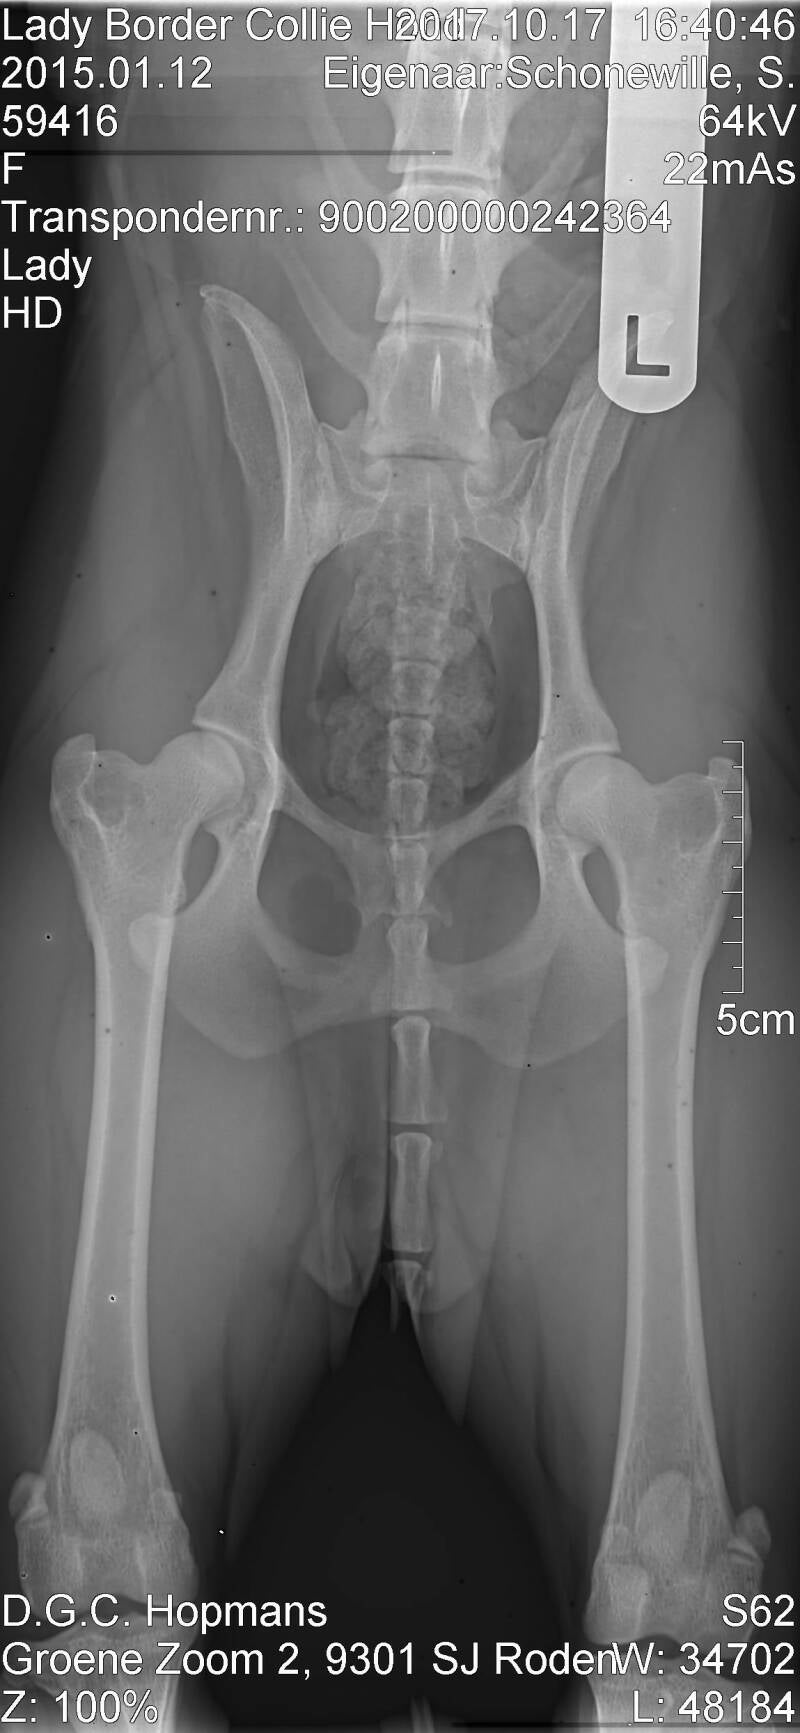

Uitslag testen: Hd A,  Pra/Cea vrij, Dna Cea clear